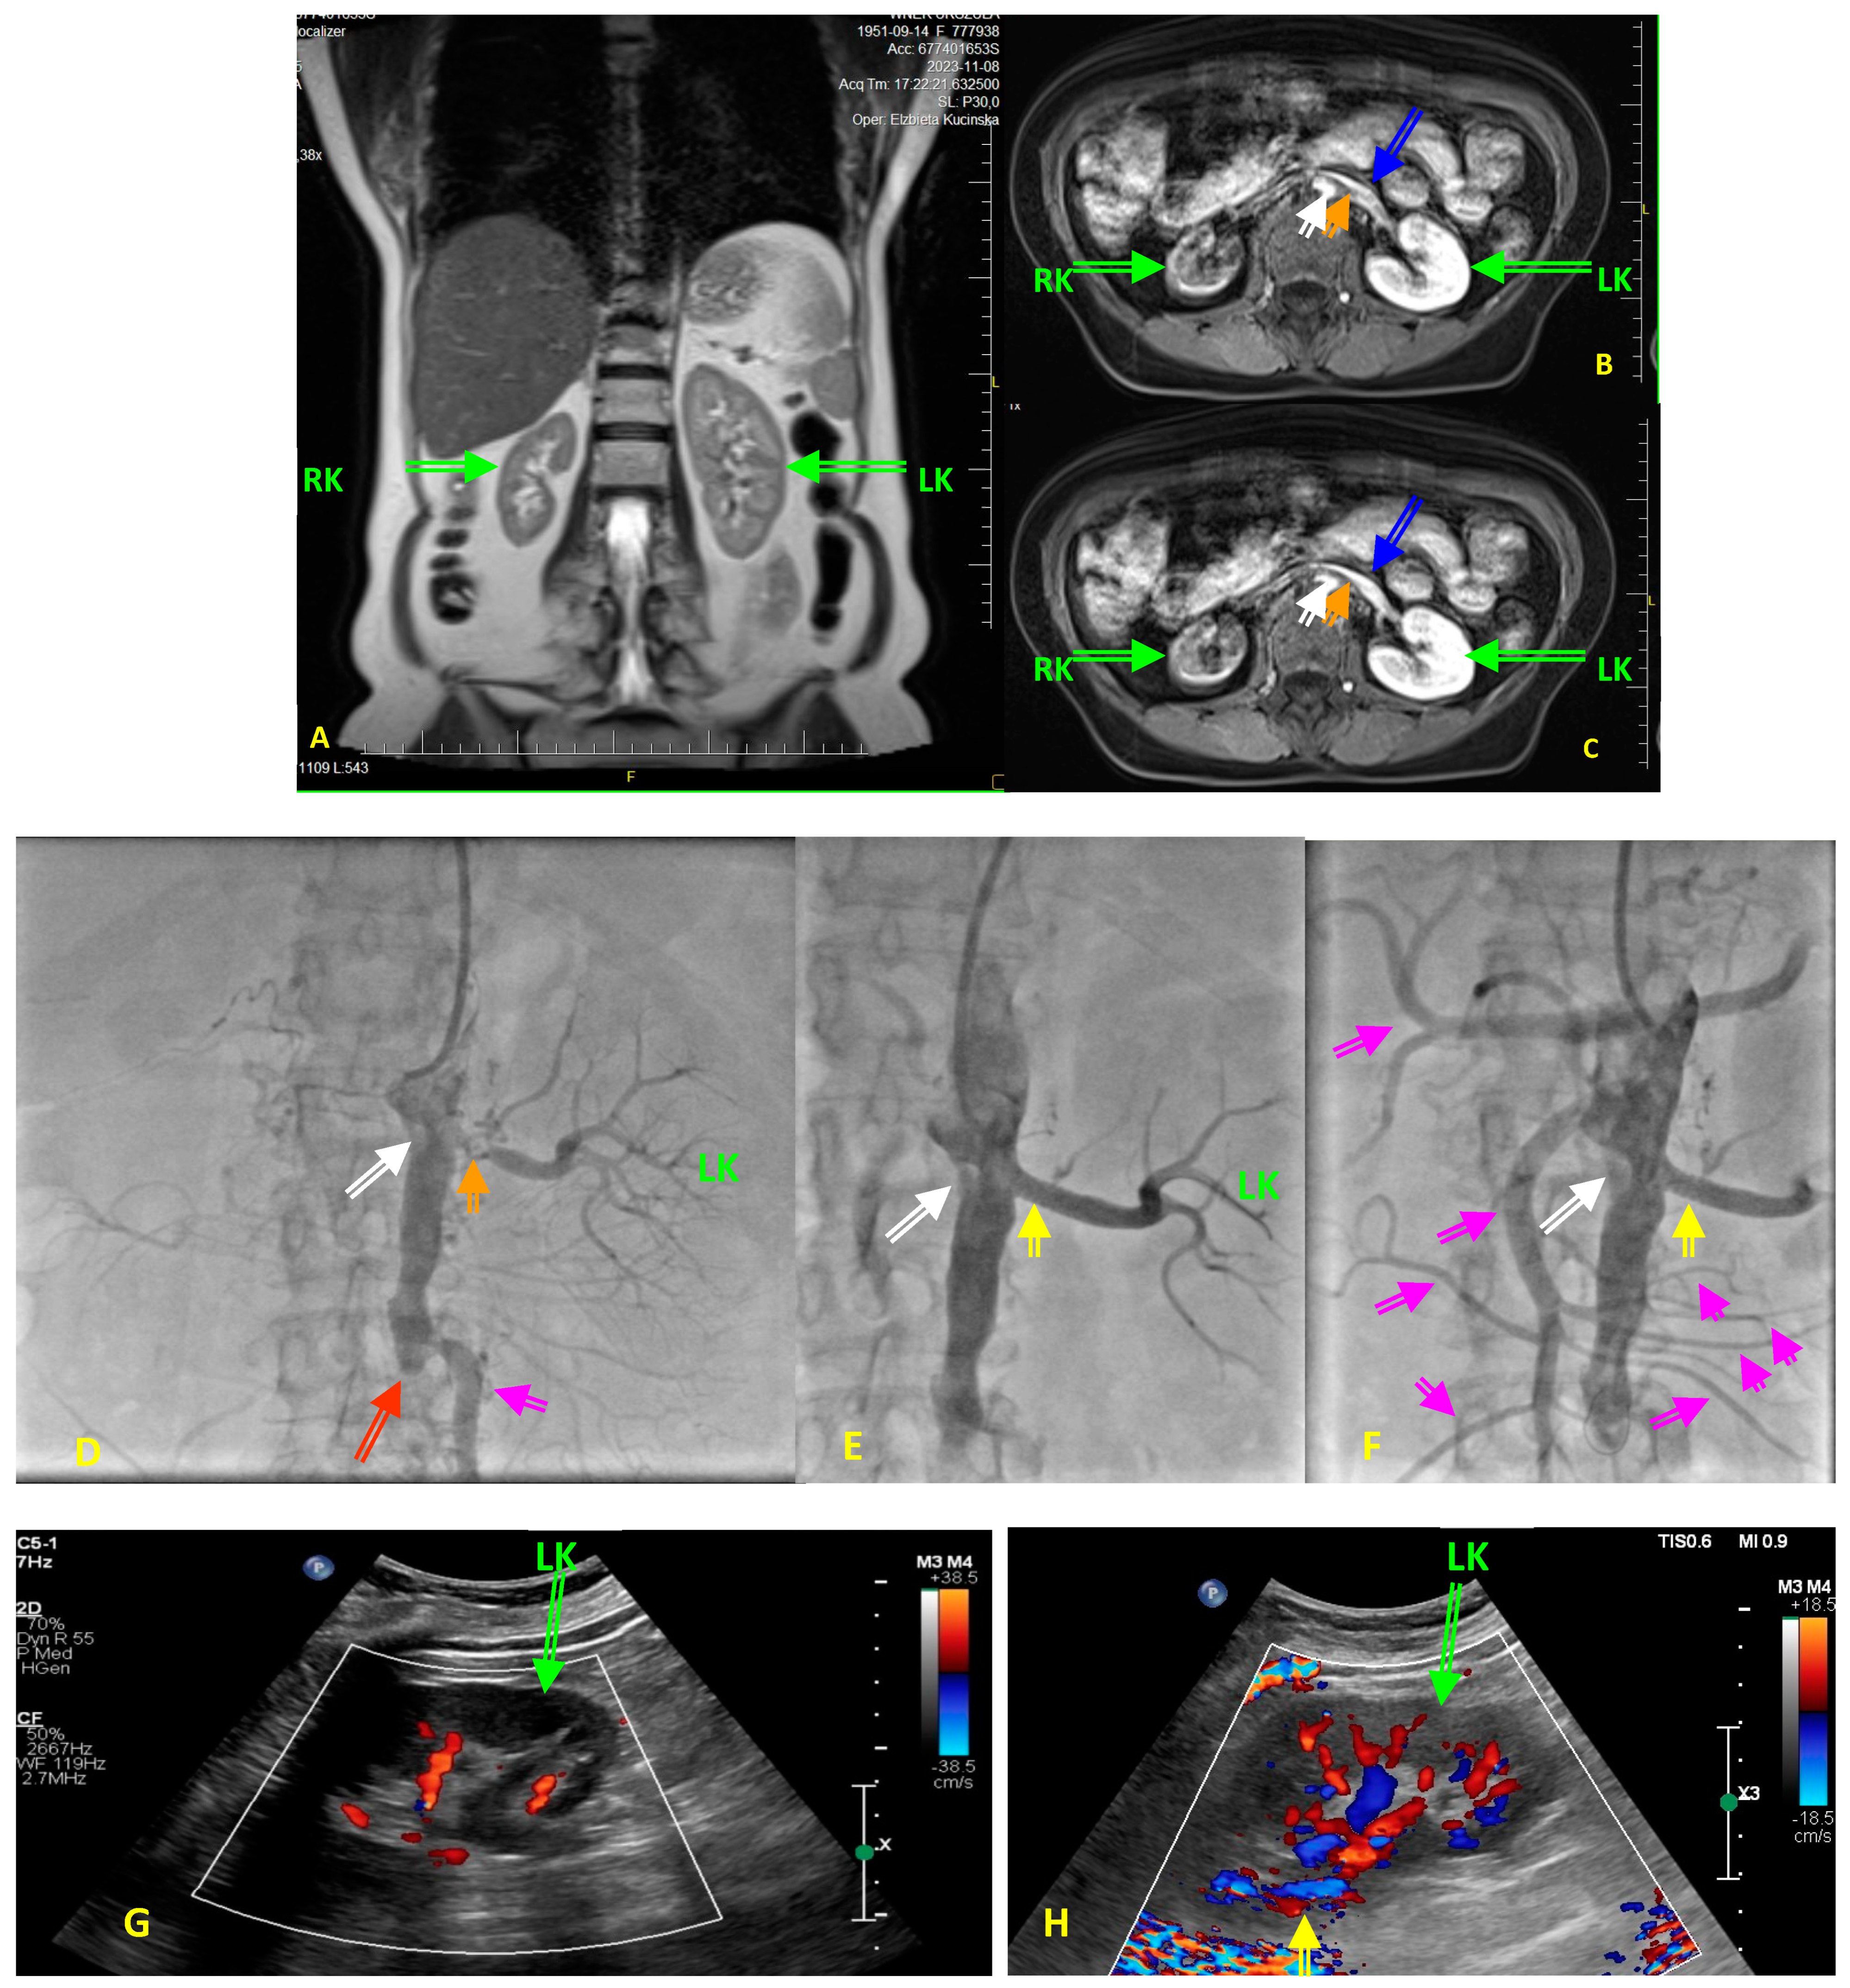

| Diversities in the elderly patients | Severely calcified atherosclerotic lesions; stenosis in more than one carotid/vertebral artery; excessively elongated vessels, often with loop formation or acute angles <90%; high arterial stiffness and raised vascular resistance; atherosclerotic lesions in intracranial segments and cerebral arteries. | Diffuse, multilevel atherosclerotic lesions, also involving the tibiofemoral trunk and arteries below the knee; development of collateral circulation. In diabetics, superimposed lesions of diabetic angiopathy and peripheral neuropathy, hyalinization of the endothelium, ulcerations, trophic changes, reddening of the toes, and gangrene. | Stable atherosclerotic lesions, with a similar degree of progression and lumen reduction to those before age 70, but less prone to rupture and thrombosis. More fibrous components and calcification in plaques, fewer inflammatory cells and lower lipid composition, regression of necrotic and lipid core, better developed peripheral circulation. | Active atherosclerotic lesions, often coexisting with advanced atherosclerotic lesions in the coronary, carotid/vertebral arteries; abdominal aortic aneurysm and Leriche syndrome. | |

| Typical clinical manifestation in the elderly | Often | Dizziness, memory impairment, tinnitus, progressive deterioration of cognitive functions, dementia, general disability, falls and their consequences, increasing frailty syndrome, stroke from large extracranial arteries. | Asymptomatic or mild intermittent claudication, whole-leg fatigue, numbness, leg pain on palpitation, hypoesthesia. | Dyspnea, easy fatigue, palpitations, atrial and ventricular arrhythmia chronic coronary syndrome, increasing symptoms of HF, reduced exercise tolerance. | Sudden worsening of blood pressure control, increasing symptoms of HF, decreased exercise tolerance, angina complaints, escalation of ACEI/ARB doses may cause acute renal failure, progression of of renal failure. |

| Infrequently | Asymptomatic course. | Critical ischemia, acute lower limb ischemia, gangrene, non-healing ulcers, amputation. | Acute coronary syndrome with ST-segment elevation. | Pulmonary flash oedema, chronic coronary syndrome, acute renal failure. | |

| Predominant mechanism of acute ischemia of the supplied organ | Often | Embolization of cerebral arteries, facilitated by the morphology and histopathological composition of the plaque and the distribution of stress shear forces resulting from the anatomy of the carotid artery bulb, 70–80%. | Decrease in blood flow, e.g., due to patient dehydration, infection, or calcification of the intimal layer. Obstruction of small peripheral arteries (favored by diabetes, dialysis). | Acute arterial occlusion due to plaque rupture and thrombus formation, 80–90%, mainly in men, often in women over the age of 60–65 years and above. | Hypertensive crisis, pulmonary oedema, acute circulatory failure. |

| Rarely | Acute arterial occlusion due to plaque rupture and thrombus formation, 10–20%. Hypoperfusion mechanism, 5–10% (older people tend to have well-developed collateral cerebral circulation). | Non-atherosclerotic acute limb ischemia (e.g., cardiogenic embolism—thrombus, myxoma). Plaque rupture and thrombus (usually well-developed collateral circulation protects against acute lower limb ischemia). | Microvascular embolism—ulcerated plaques rich in proteoglycans, 10–20%, common etiology in women before the age of 60–65 years. | Acute renal ischemia—generally renal failure progresses slowly in a chronic manner—it is estimated that in about 20% of chronic dialysis patients, the cause is renal artery stenosis/obstruction. | |

| Warning signs in the elderly | Syncope, loss of consciousness, dysregulation of previously well-controlled blood pressure. Other typical—transient limb weakness, amaurosis fugax, features of facial nerve palsy, hemiparesis. | Forced posture with the lower limb lowered (alleviates subjective symptoms of critical ischemia), inability to put the leg up (increases pain), swelling of the lower limb, ulceration, skin atrophy, redness and gangrene of the fingers. | Chest pain, sweating, pulmonary oedema, new-onset left bundle branch block on ECG, fatigue, nausea, abdominal pain. Chest pain is not always typical and characteristic | Dysregulation of previously well-controlled blood pressure, rapidly progressive renal failure, decreasing renal dimension on subsequent ultrasound examinations, 20–30% decline in eGFR after starting ACEIs, ARBs or SGLT2 inhibitors. | |

| Methods of diagnosing atherosclerotic lesions in older people | Preferred | Doppler-duplex ultrasound—good resolution, no need for a contrast agent. Limitation—calcifications causing an acoustic shadow make it difficult to assess the vessel lumen. CT and MRI of the brain—diagnosis of ischemic lesions. | Doppler-duplex ultrasound—good resolution, no need for a contrast agent. Limitation—calcifications giving an acoustic shadow make it difficult to assess the vessel lumen. ABI indicates lower limb atherosclerosis when it is <0.9, but it is often nondiagnostic in people with diabetes due to intimal calcifications (ABI > 1.4). TBI in patients with diabetes and non-diagnostic ABI (>1.4); TBI < 0.7 is diagnostic for PAD. Pulse oximetry—measurement of blood pressure on the toe—a prognostic indicator of ulcer healing. | Treadmill test—assessment of exercise tolerance and detection of new ischemic changes. Echocardiography—assessment of left ventricular systolic function; wall motion abnormalities; diastolic function; exclusion of intracardiac problems such as thrombus, valve disease, pericardial effusion, features of pulmonary embolism. SPECT—assessment of viability and ischemic area on isotope. | Doppler-duplex ultrasound—good resolution, no need for a contrast agent. Limitation—obesity makes the examination difficult/impossible. |

| Limited | CTA—anatomical assessment, but test affects renal and thyroid function, caution if renal failure with eGFR below 50 mL/min/kg, calcifications make assessment of vascular stenosis difficult. MRA—anatomical assessment, possible assessment of plaque morphology, but long examination, requires administration of gadolinium (caution if eGFR < 30 mL/min); claustrophobia. | CTA—anatomical assessment, but test affects renal and thyroid function; caution if renal failure with eGFR below 50 mL/min/kg, calcifications make assessment of vascular stenosis difficult. MRA—anatomical assessment; possible assessment of plaque morphology, but long examination, requires administration of gadolinium (caution if eGFR < 30 mL/min); claustrophobia. | CTA—anatomical assessment, but test affects renal and thyroid function; caution if renal failure with eGFR below 50 mL/min/kg; calcifications make assessment of vascular stenosis difficult. MRA—anatomical assessment; possible assessment of plaque morphology, but long examination, requires administration of gadolinium (caution if eGFR < 30 mL/min); claustrophobia. | CTA offers anatomical assessment, but it affects renal and thyroid function; caution if renal failure with eGFR below 50 mL/min/kg; calcifications make assessment of vascular stenosis difficult. MRA—anatomical assessment; possible assessment of plaque morphology, but long examination, requires administration of gadolinium (caution if eGFR < 30 mL/min); claustrophobia. Scintigraphy with captopril test—not recommended for diagnosis of RAS (class III recommendation). Renal vein renin activity assessment—not recommended (class III recommendations). | |